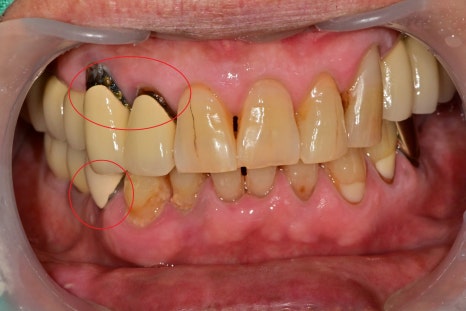

빨간 원으로 표시된 치아 중에서도

위 치아의 크라운 주변 치아가 이미 육안으로도

2차 충치가 많이 진행되어 보입니다.

환자분께서도 심미적으로도 좋지 않기 때문에 최대한 다시 씌워서 사용하고 싶다고 하셨습니다.